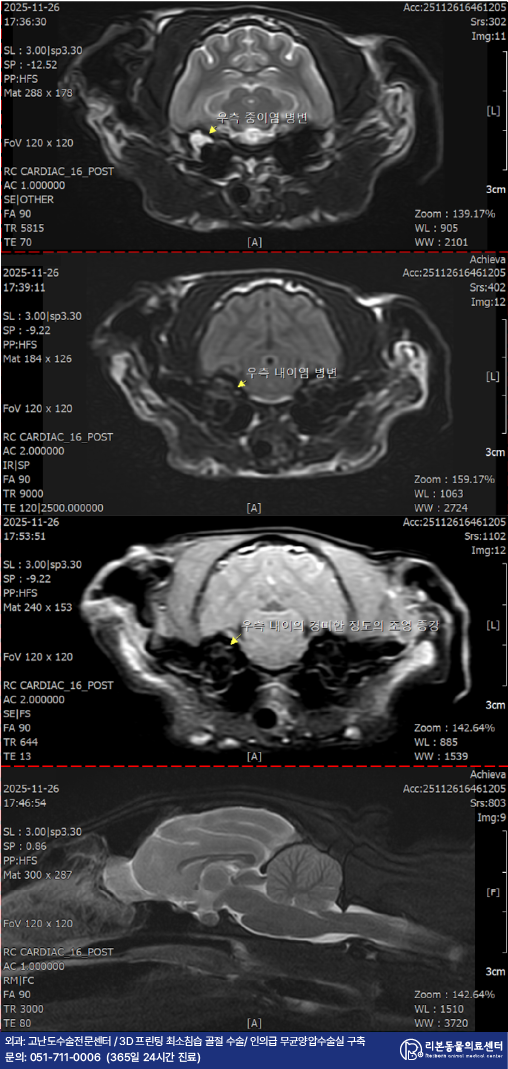

간단한 마취전 검사 후 진행된 MRI 촬영 상 중이 내의 다량의 삼출물과 중이, 내이의 염증 소견이 관찰되었습니다.

이는 중이염/내이염을 지시하는 강력한 근거로 환자의 전정계 증상은 중이염/내이염에 의한 것으로 진단되었습니다.

다행히 환자의 소뇌, 뇌간 등 전정계를 담당하는 중추에 병변은 관찰되지 않았습니다.